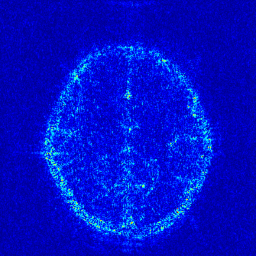

We take the difference between the absolute reconstruction error of zero-filled and the compared CS-MRI methods and only keep the nonnegative values, which can be formulated as

md=(|xfsx¯p||xfs𝒵(y)|)+.subscript𝑚𝑑subscriptsubscript𝑥𝑓𝑠subscript¯𝑥𝑝subscript𝑥𝑓𝑠𝒵𝑦m_{d}={\left({\left|{{x_{fs}}-{\overline{x}_{p}}}\right|-\left|{{x_{fs}}-{\cal Z}(y)}\right|}\right)_{+}}. (8)

Where the operator ()+subscript{\left(\cdot\right)_{+}} set the negative values to zero. We only keep the nonnegative values in the map, which results the filtered difference map. We show the corresponding filtered difference map mdsubscript𝑚𝑑m_{d} in figure 3 in the range [0 0.2]. The bright region means the better accuracy of zero-filled reconstruction. We observe the zero-filling reconstruction provide better reconstruction accuracy on some regions, indicating the information loss in the reconstruction occurs.

Figure 3: The filtered difference map d𝑑d between the reconstruction errors of the zero-filled reconstruction and recent CS-MRI inversions.